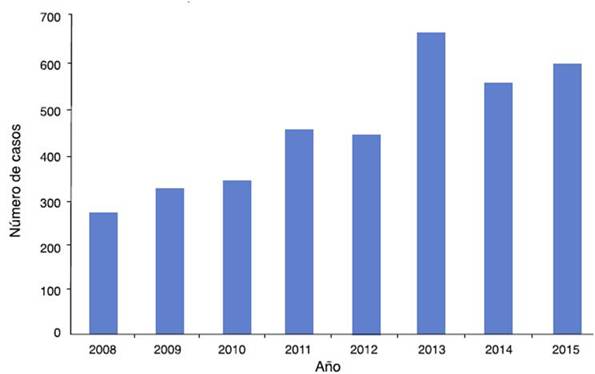

En México, a pesar de que se ha incrementado el número de pacientes diagnosticados con EK, hasta el momento no se cuenta con una casuística real de la enfermedad ya que sigue siendo una enfermedad subdiagnosticada. De acuerdo a los datos obtenidos de la Dirección General de Información en Salud de la Secretaría de Salud existe un incremento significativo en el número de casos de EK diagnosticados en los últimos años17 (fig. 2).

Figura 2 Número de egresos hospitalarios en México en pacientes con diagnóstico de enfermedad de Kawasaki (CIE M303. Síndrome linfomucocutáneo) por año. Fuente: Dirección General de Información en Salud (DGIS). Secretaría de Salud, México17.